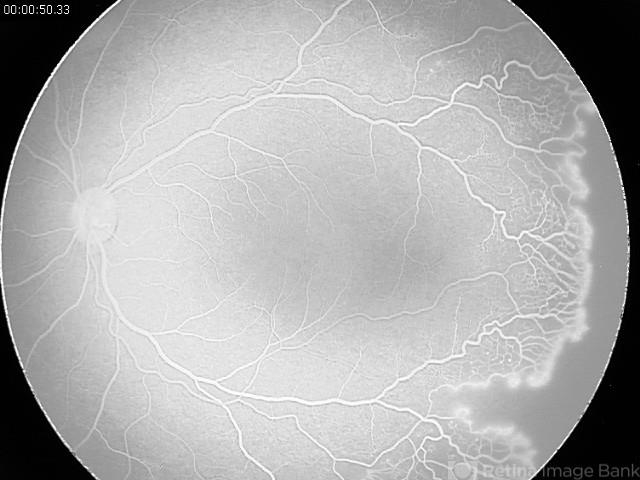

- Oxygen toxicity retinopathy

- retinopathy of prematurity (ROP)

- Angiogram taken on a 42 weeks corrected age baby born at 34 weeks. The baby developed lung disease and received oxygen 100% for 4 weeks.